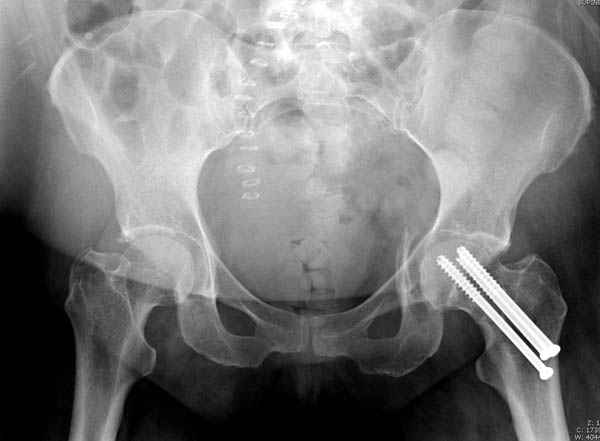

В положении на спине подвздошным и надлобковым доступом восстанавливается тазовое кольцо, фиксация пластинами. При хорошей репозиции может улучшиться конгруэнтность в суставе.

Затем, если положение хорошее, закрытый остеосинтез шейки винтами.

Если нет - в положении на боку, синтез задней колонны из наружно-латерального доступа и синтез головки винтами, но уже под визуальным контролем.

На картинке подобный случай, только без шейки, сделано через месяц или полтора после травмы.